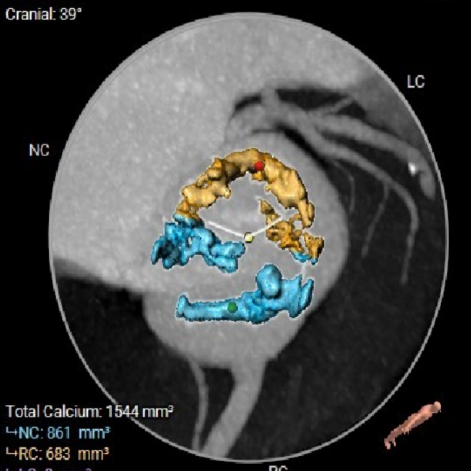

● Type 0型二叶式主动脉瓣,重度钙化,钙化分布于窦内,钙化分布均匀,瓣叶对合缘处存在钙化黏连和不规则纤维增厚,LVOT呈收口形;

HU850

图片

术前考虑右侧股动脉为主入路,左侧为辅助入路。非横位心,主动脉弓角度、宽度尚可,预估输送器过弓难度适宜,跨瓣难度适宜,术中必要时采用Snare辅助。左右冠脉开口高度可,左冠切线角度测量瓣叶大于LCA开口下缘到根部距离,结合瓦氏窦及STJ尺寸预估,冠脉风险适中,建议术中密切关注左冠灌注情况。外周入路走行适宜,腹主中下端和左右髂总散在钙化,血管内径尚可,血管内壁存在不规则纤维增厚和钙化斑,入路穿刺规范操作,小心通过,避免入路血管损伤及相关并发症。重度钙化二叶式病变重度主动脉瓣狭窄,其瓣口面积小,瓣口限制明显,术中瓣膜锚定难度较大,瓣膜植入受二叶瓣瓣叶及团块状钙化挤压存在移位及少量偏多瓣周漏风险,为避免手术并发症,手术预装AV26瓣膜,根据20mm球囊预扩结果选择瓣膜型号,计划瓣膜瓣上3mm开始释放。